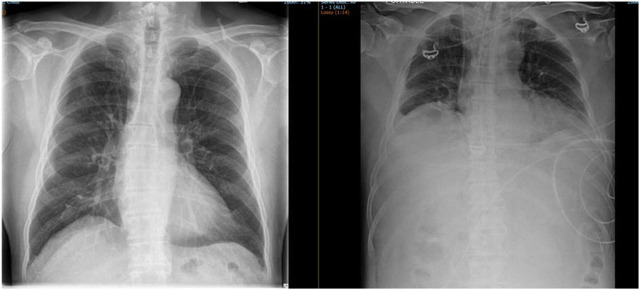

Case presentation: A 74-year-old male with diabetes and hypertension underwent HoLEP for a 180-ml prostate, during which 106 liters of normal saline irrigation were used over three hours. Intraoperatively, the patient developed sudden respiratory distress and hypotension, with arterial blood gas analysis revealing severe metabolic acidosis (pH 7.141, HCO3 11 mEq/L, Cl 115 mEq/L), primarily due to excessive saline absorption and hyperchloremia. The patient required intubation, vasopressor support, and emergency dialysis due to worsening hemodynamic instability. Postoperative imaging revealed intra-abdominal fluid collection, which was drained percutaneously. After two days of intensive ICU management, the acidosis resolved, and the patient was successfully extubated.